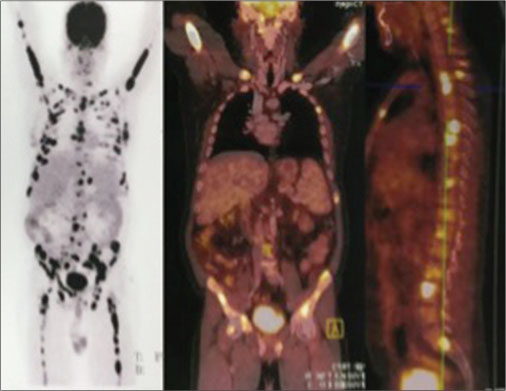

A 43-year-old male patient underwent deceased-donor liver transplantation in June 2012 for the Budd Chiari syndrome. Four years later, he presented with colicky abdominal pain. On examination, the vague nontender mass was found in the right periumbilical and iliac region. Complete blood counts showed hemoglobin of 14 gm/dl, total leukocytes count of 4900/cu mm, and platelet count of 1,89,000/mL. Liver function test revealed total bilirubin of 0.9 mg/dl with direct bilirubin-0.4 mg/dl, alanine transaminase- 64 U/L, aspartate transaminase-55U/L, alkaline phosphatase-78U/L, gamma-glutamyl transferase-78U/L, total protein-7.8 gm/dl, albumin-4gm/dl, internationalized ratio (1.4), serum creatinine-0.7 mg/dl, and blood tacrolimus level of 7 ng/ml. The patient was IgG EBV-positive. Ultrasound abdomen revealed an approximately 5.8 cm ? 3.7 cm ? 3.5 cm sized lesion composed of bowel with the asymmetrically thickened wall in the right iliac fossa. Contrast-enhanced computed tomography (CT) of abdomen revealed thickening of ileum for a length of 6 cm without obstruction. While performing colonoscopy, the distal involved part of the ileum could not be reached. Resection and end-to-end anastomosis was planned. Routine workup for surgery revealed hepatitis B positivity (which was negative before transplant). Mass which was situated about 50 cm from the ileocecal junction was removed, and jejunum to ileal anastomosis was done. Histopathology of small bowel mass showed intermediate-sized, noncleaved, lymphoid cells with high proliferation rate suggestive of Non-Hodgkin?s lymphoma of Burkitt type [Figure 1] with immunohistochemistry positive for CD 10, CD20, BCL-6, and C-myc. Tumor cells also expressed Epstein-Barr encoding region by?in situ?hybridization. They were immune-negative for CD3, MUM-1, and BCL 2. The Mib-1 proliferation index was approximately 100%. Positron emission tomography-CT (PET-CT) revealed hypermetabolic solid adrenal nodule on the left side, most likely suggestive of lymphomatous involvement. Hypermetabolic osseous foci were seen disseminated throughout axial and appendicular skeleton involving the bilateral humeri, clivus, right temporal bone, bilateral clavicles, scapulae, sternum, vertebra, multiple ribs, sacrum, pelvic bones and bilateral femora, SUVmax of reference focus in the right humerus was 22.73, most likely of lymphomatous involvement [Figure 2]. Quantitative polymerase chain reaction (PCR) for EBV revealed 2517 copies/ml. Biopsy from left iliac bone was also suggestive of BL. Bone marrow aspiration done showed basophilic cells with vacuolated cytoplasm, which was suggestive of involvement by BL. The patient was treated with chemoimmunotherapy with three cycles of rituximab, cyclophosphamide, adriamycin, vincristine, and prednisolone with intrathecal methotrexate along with tumor lysis syndrome prophylaxis. After three cycles of chemoimmunotherapy, PET-CT scan revealed complete metabolic and morphologic resolution of the left adrenal gland nodule and skeletal lesions. Very low-grade fluorodeoxyglucose uptake was seen at the sites of increased metabolic activity seen earlier in the musculoskeletal system [Figure 3].

|?Figure. 3? The positron emission tomography-computed tomography showing complete metabolic and morphological resolution in bones and left adrenal gland